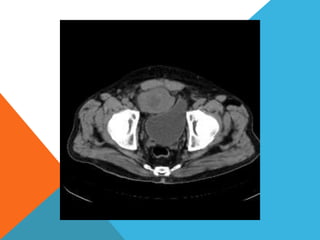

El paciente presentó síntomas de sangrado digestivo y pérdida de peso. Exámenes revelaron gastritis crónica asociada a H. pylori. Un tumor fue descubierto en una colonoscopia normal. La cirugía removió un tumor fibroide solitario, una rara neoplasia mesenquimal que usualmente crece lento y tiene bajo potencial de malignidad. El pronóstico después de la remoción quirúrgica es generalmente bueno.